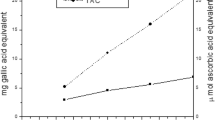

The effects of quercetin on CCl4-induced lipid peroxidation products, measured as TBARS in the liver, are reported shown in Table 3. CCl4 significantly increased the TBARS concentration, by 98%, but quercetin inhibited it by 26%, compared with that in the CCl4 group.

CCl4 significantly decreased the hepatic GSH concentration, by 10%, compared to that in the control group, but when quercetin was also administered, the GSH concentration was maintained at the level detected in the control group (Table 3).

Antioxidant enzyme (SOD, CAT, GPx, GST) activities were significantly different between the CCl4 and the CCl4 + quercetin groups (Table 3). Compared to the control group, CCl4 administration significantly decreased SOD activity in the liver, by 63%, while quercetin administration increased it to 70% compared with that in the CCl4 group (Table 3). Likewise, CCl4 significantly decreased CAT (67%), GPx (68%), and GST (58%) activities in the liver, which were restored by quercetin administration to 77%, 54%, and 52%, respectively, compared to those in the CCl4 group.

LPO determines alterations in structures and cell membranes by two mechanisms: (1) covalent binding with cell macromolecules and (2) action on lipids [38]. The animals receiving CCl4 presented elevated LPO (70%). This is a result of CCl4 metabolization by cytochrome P-450, which yields two such highly toxic radicals as CCl3 • and CCl3O2 • [39]. Administration of quercetin to the animals determined a 26% reduction in LPO. Quercetin’s possible mechanism of action is through the improvement of damage caused by CCl4, preventing injuries by the generated radicals. Quercetin can act as a scavenger of CCl3 •.

GSH is a major antioxidant and its levels can be altered by various chemical agents such as CCl4. GSH is produced in the liver and is kept at high levels in most tissues. Normally there is more GSH and GSSG within the cell than in the plasma, something which does not occur during liver injury processes [41]. In our work, GSH levels were found to be decreased in cirrhotic animals, similar to reports by other authors [34, 42–45]. The administration of quercetin was able to restore GSH levels to those in the control group. These results are close to those reported by Lee et al. [46], who administered quercetin orally in order to reduce dimethylnitrosamine-induced liver injury. Those authors noted that quercetin produced an increase in serum albumin and liver GSH levels and a decrease in lipid peroxidation, data similar to those found in our work.

In our study, SOD and CAT were significantly decreased [63%] compared to those in controls and were elevated in animals receiving quercetin, an increase of 70% for SOD and of 77% for CAT. These results match those of previous work [47–49] showing a significant increase in the activity of these enzymes when CCl4-intoxicated animals were treated with antioxidants. Other authors have observed an increase in these enzymes also when PMC (2,2,5,7,8-pentametyl-6-hydroxychrome), a derivative of α-tocopherol, was administered [47]. Other antioxidant enzymes were evaluated in this work, such as GPx and GST. Under oxidative stress conditions, the GSH consumed by these enzymes tries to eliminate CCl4 toxicity. In this case, GPx and GST activities are decreased. In animals treated with quercetin, a reduction in oxidative damage was observed, with regeneration of GSH, and an increase in the activity of antioxidant enzymes. GPx activity is significantly reduced in animals with CCl4-induced cirrhosis compared with the control group, possibly because of the increase in superoxide and hydrogen peroxide anions resulting from the action of xenobiotics.